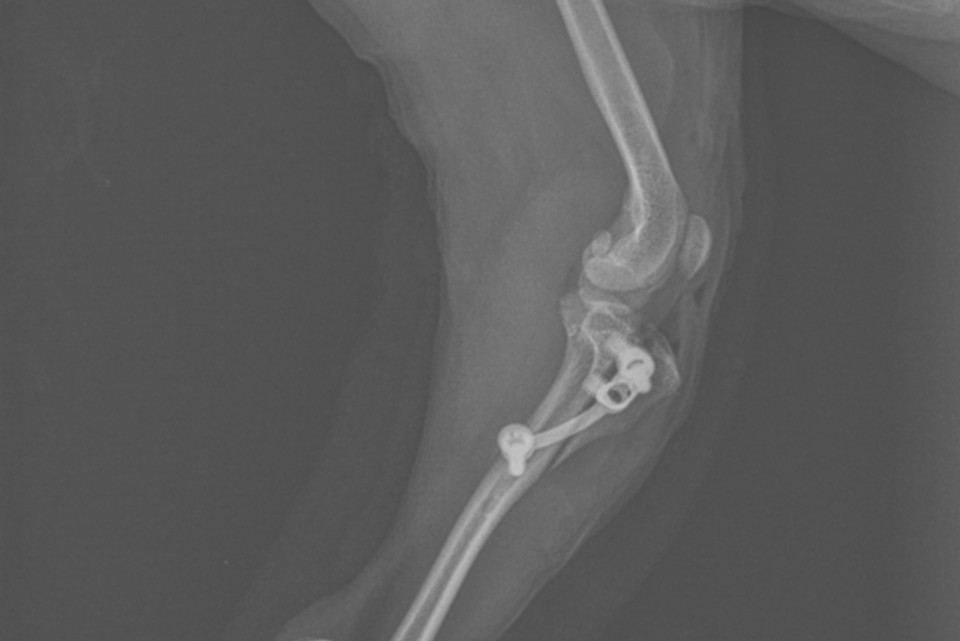

Im zweiten Teil wird die Tub. Tibiae versetzt und fixiert, um den Ansatzpunkts des gerade Kniescheibenbands und somit den Halt der Kniescheibe in seiner Führungsrinne zu verbessern (Tuberositastransposition). Methode mit Pins oder SPP-System.